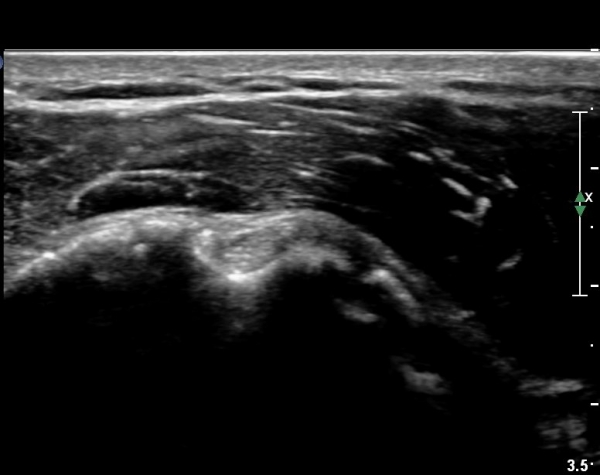

°ß°©ÇÏ±Ù°Ç ÁߺΠÁ¾´Ü¸é°Ë»ç¿¡¼­ ƯÀÌ ¼Ò°ßÀ» º¸ÀÌÁö ¾ÊÀ¸³ª(»çÁø 2) ŽÃËÀÚ¸¦ Á¶±Ý ÇϹæ(´Ù¸®ÂÊ)

À¸·Î À̵¿ÇÏ´Ï °ß°©Çϱٰdz»  ¼®È¸È­ µ¢¾î¸®°¡ °üÂûµÈ´Ù(»çÁø 3).